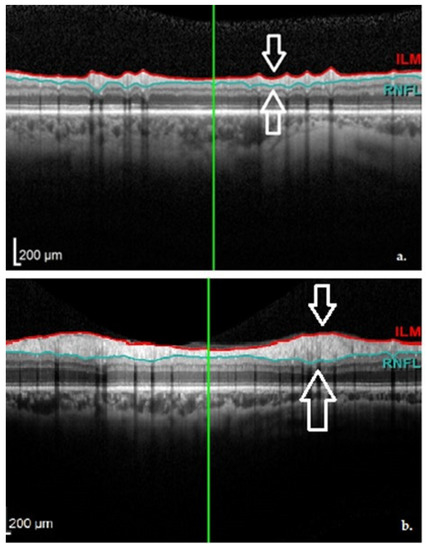

In 2014, Jimenez and colleagues studied the cpRNFL of 52 PD patients compared to healthy controls, and came up with a potential valuable formula that could predict disease severity. This was possible because of their observation that the cpRNFL gradually diminishes with the disease evolution. They also believed that OCT measurements could be useful tools in differentiating PD (see Figure 5) from other diseases, such as essential tremor [12]. This study, however, showed no correlation between the Hoehn−Yahr stage and the global cpRNFL value (µm) with r = 0.121 in the PD sample.

Figure 5. OCT aspect of the RNFL demonstrating thinning in a PD patient (a) and normal thickness in a healthy subject (b). Images from personal casuistry.